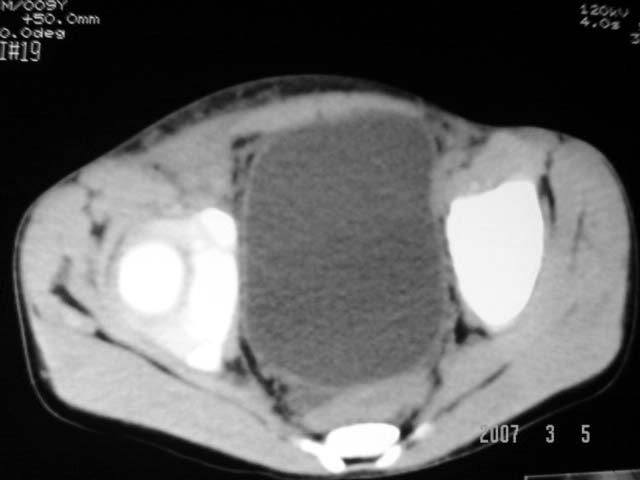

以下是引用dyqct在2007-3-5 10:28:00的发言:[br]右髂窝肿块。[br][br][br][br]